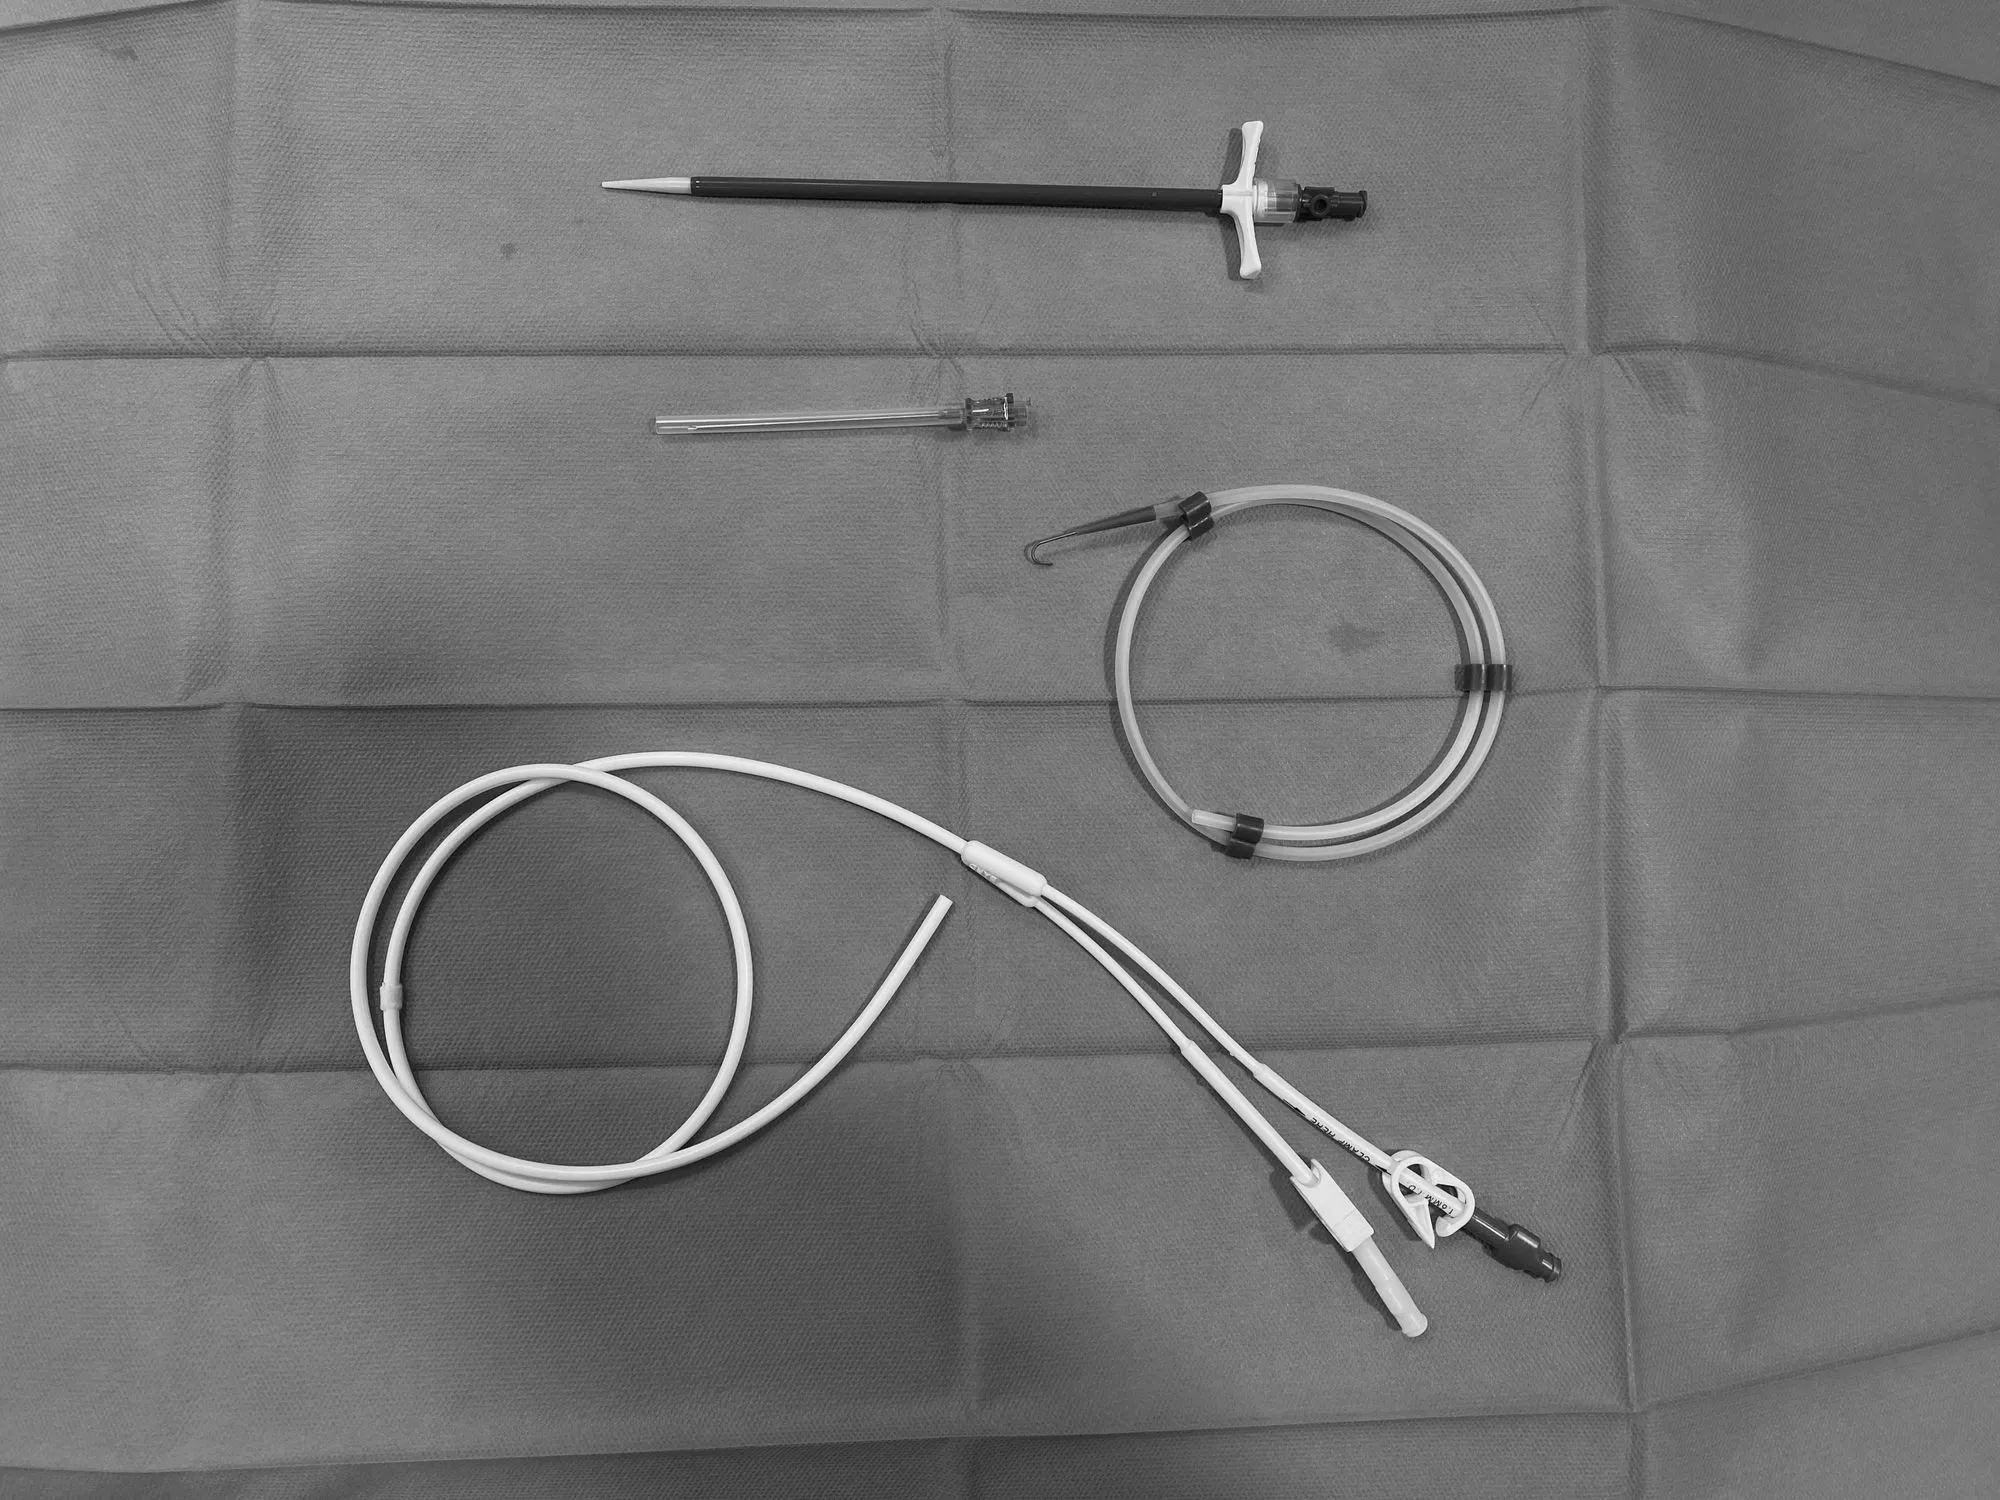

We have developed a series of  eLearning materials to facilitate student learning of radiographic assessment of lines and tubes and their potential complications.In this project, lines and tubes covered include: percutaneous central venous catheters, Port-a-Caths, Hickman lines, peripherally inserted central venous catheters (PICC lines), endotracheal tubes(ETT), amongst others.

A flipping card game to associate the purposes and appearances of different lines and tube type